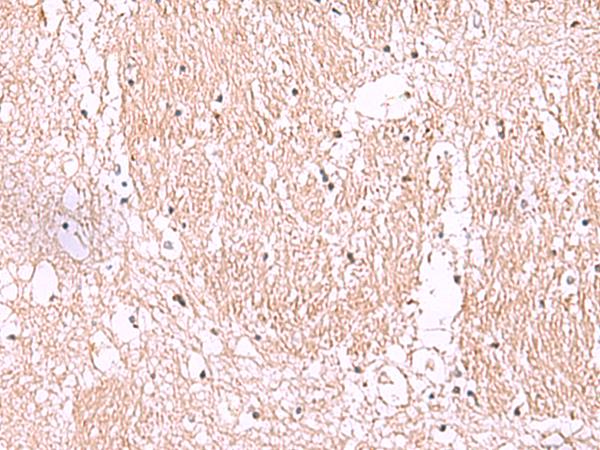

The image is immunohistochemistry of paraffin-embedded Human brain tissue using (RIC8A Antibody) at dilution 1/55. (Original magnification: ×200)